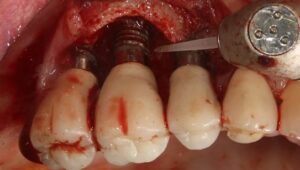

Au stade de « péri-implantite » il s’agit d’une atteinte inflammatoire des tissus mous entourant un implant. Le diagnostic clinique comprend un saignement au sondage, avec une suppuration quasi systématique, et une profondeur de poche péri-implantaire supérieure ou égale à 5 mm. Radiographiquement, un aspect radioclair de déminéralisation osseuse marginale supérieure ou égale à 2 mm entoure une partie plus ou moins étendue du corps de l’implant (fig 1 et 2).

Figure 2: aspect radiographique de la perte osseuse confirmant la péri-implantite

• un traitement comprenant un débridement mécanique, suivi d’un aéropolissage poudre d’air avec de la glycine (fig. 7), suivi d’un conditionnement d’acide citrique ou d’eau oxygénée à 10 volumes avec un rinçage vigoureux de la surface implantaire à l’eau stérile après chaque étape, serait capable de décontaminer la surface infectée. (Rosen et al 2018)

Figure 7: aéro polissage de la surface implantaire à l’aide d’une tête fine (Prophyflex Kavo), après élimination du tissu de granulation